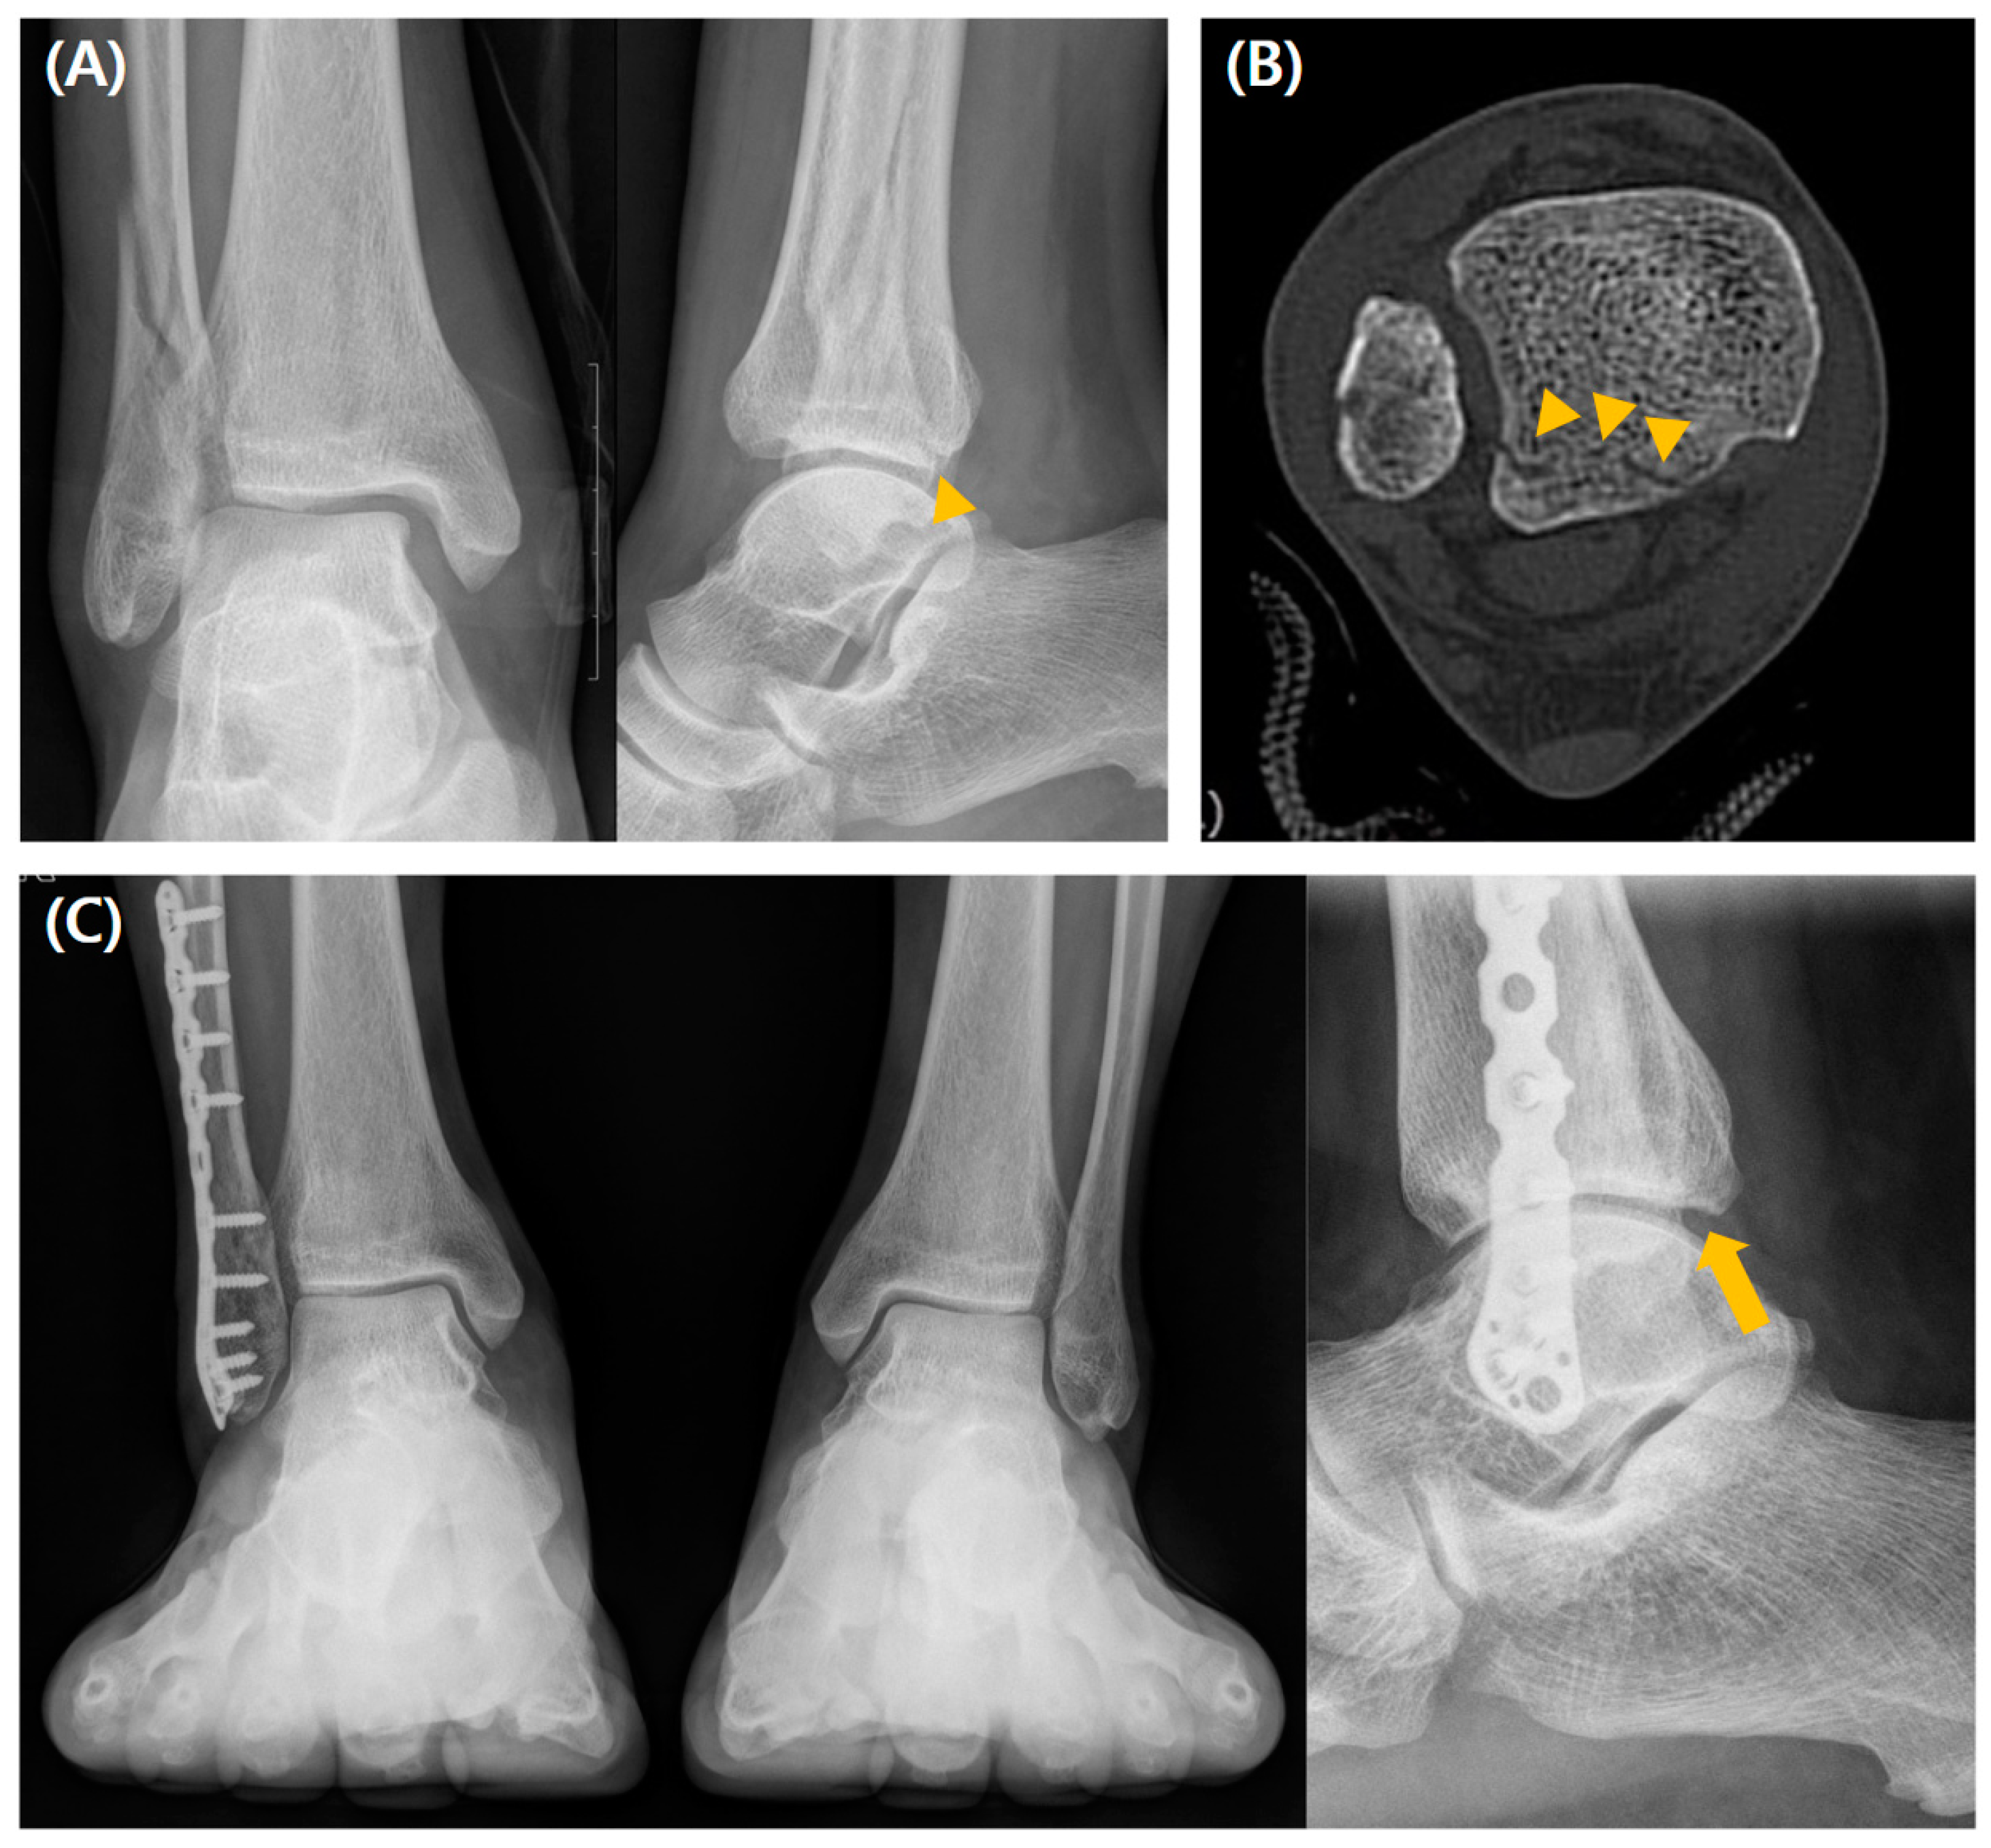

3.1. Comparison Between the Fixation and Non-Fixation Groups Within Type 1 Fracture

The intercalary fragment (ICF) assessed by preoperative CT was more frequently observed in the fixation group (p < 0.001). There were no significant postoperative intergroup differences in reduction quality assessed by immediate postoperative CT, residual step-off, or PTOA development. Moreover, there were no significant intergroup differences in the clinical values, including mean AOFAS, OMAS, FAOS, or VAS scores at the final follow-up. Postoperative complications occurred more frequently in the fixation group (37% vs. 18.6%, p = 0.008) (Table 1). A radiographic case example of a type 1 fracture is depicted in Figure 3.

In type 1 PMF, ICFs were significantly more frequent in the fixation group than in the non-fixation group. ICF might prevent the reduction of the posterior plafond and is considered a prognostic factor for PTOA development; thus, it could be addressed operatively [6,12,22]. Sultan et al. [22] suggested that ICFs < 2 mm in diameter should be considered removed, and proper reduction should be performed for those >2 mm through the posterolateral or posteromedial approach. Given the higher rate of postoperative complications in the fixation group, efforts should be made to reduce the risk of postoperative complications related to the operative procedure. Although our results showed a trend toward a higher rate of poor reduction quality and PTOA in the non-fixation group than in the fixation group, no significant intergroup differences were observed in the radiological and functional outcomes during a follow-up of >3 years. There might be situations in which the operative approach is eminently indicated, such as an ICF possibly preventing the reduction of the posterior malleolus or posterior subluxation of the talus even after syndesmotic stabilization in addition to lateral/medial malleolar reduction [13,22,35]. Except for these situations, the non-fixation method combining appropriate syndesmotic fixation might show results comparable to the operative approach for type 1 PMF.

Figure 3. A case of a 56-year-old man who underwent conservative management for type 1 PMF. (A) Preoperative radiographs show a fracture line (arrowhead), and (B) preoperative CT scan images show a posterior malleolar fragment representing a type 1 fracture line (arrowheads) without the ICF. (C) Weight-bearing radiographs obtained 3 years postoperatively show acceptable reduction and bone healing (arrow).